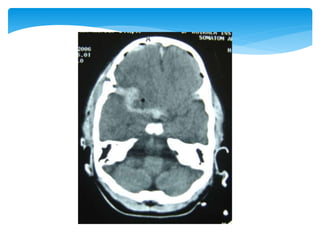

 Between thedura mater and inner table of the skull; usually in the temporal or temporoparietal region  Tearing of the middle meningeal artery or, less commonly, secondary to venous bleeding  Directly related to the status of the patient before surgery  Close to 0 for patients not in a coma, 9% for obtunded patients, and 20% for patients in deep coma Extradural Haematoma

Approach To CT ScanCT scan

Approach To CTScanCT scan Bone window Look for fractures- •Cranial vault •Skull base •Facial bones Tissue window •EDH •SDH •ICH •Contusions •Pneumocephalus •Hydrocephalus •Cerebral edema Subdural window •Any hemorrhage •Soft tissue and bone •Fontanel •Suture lines •Foreign bodies